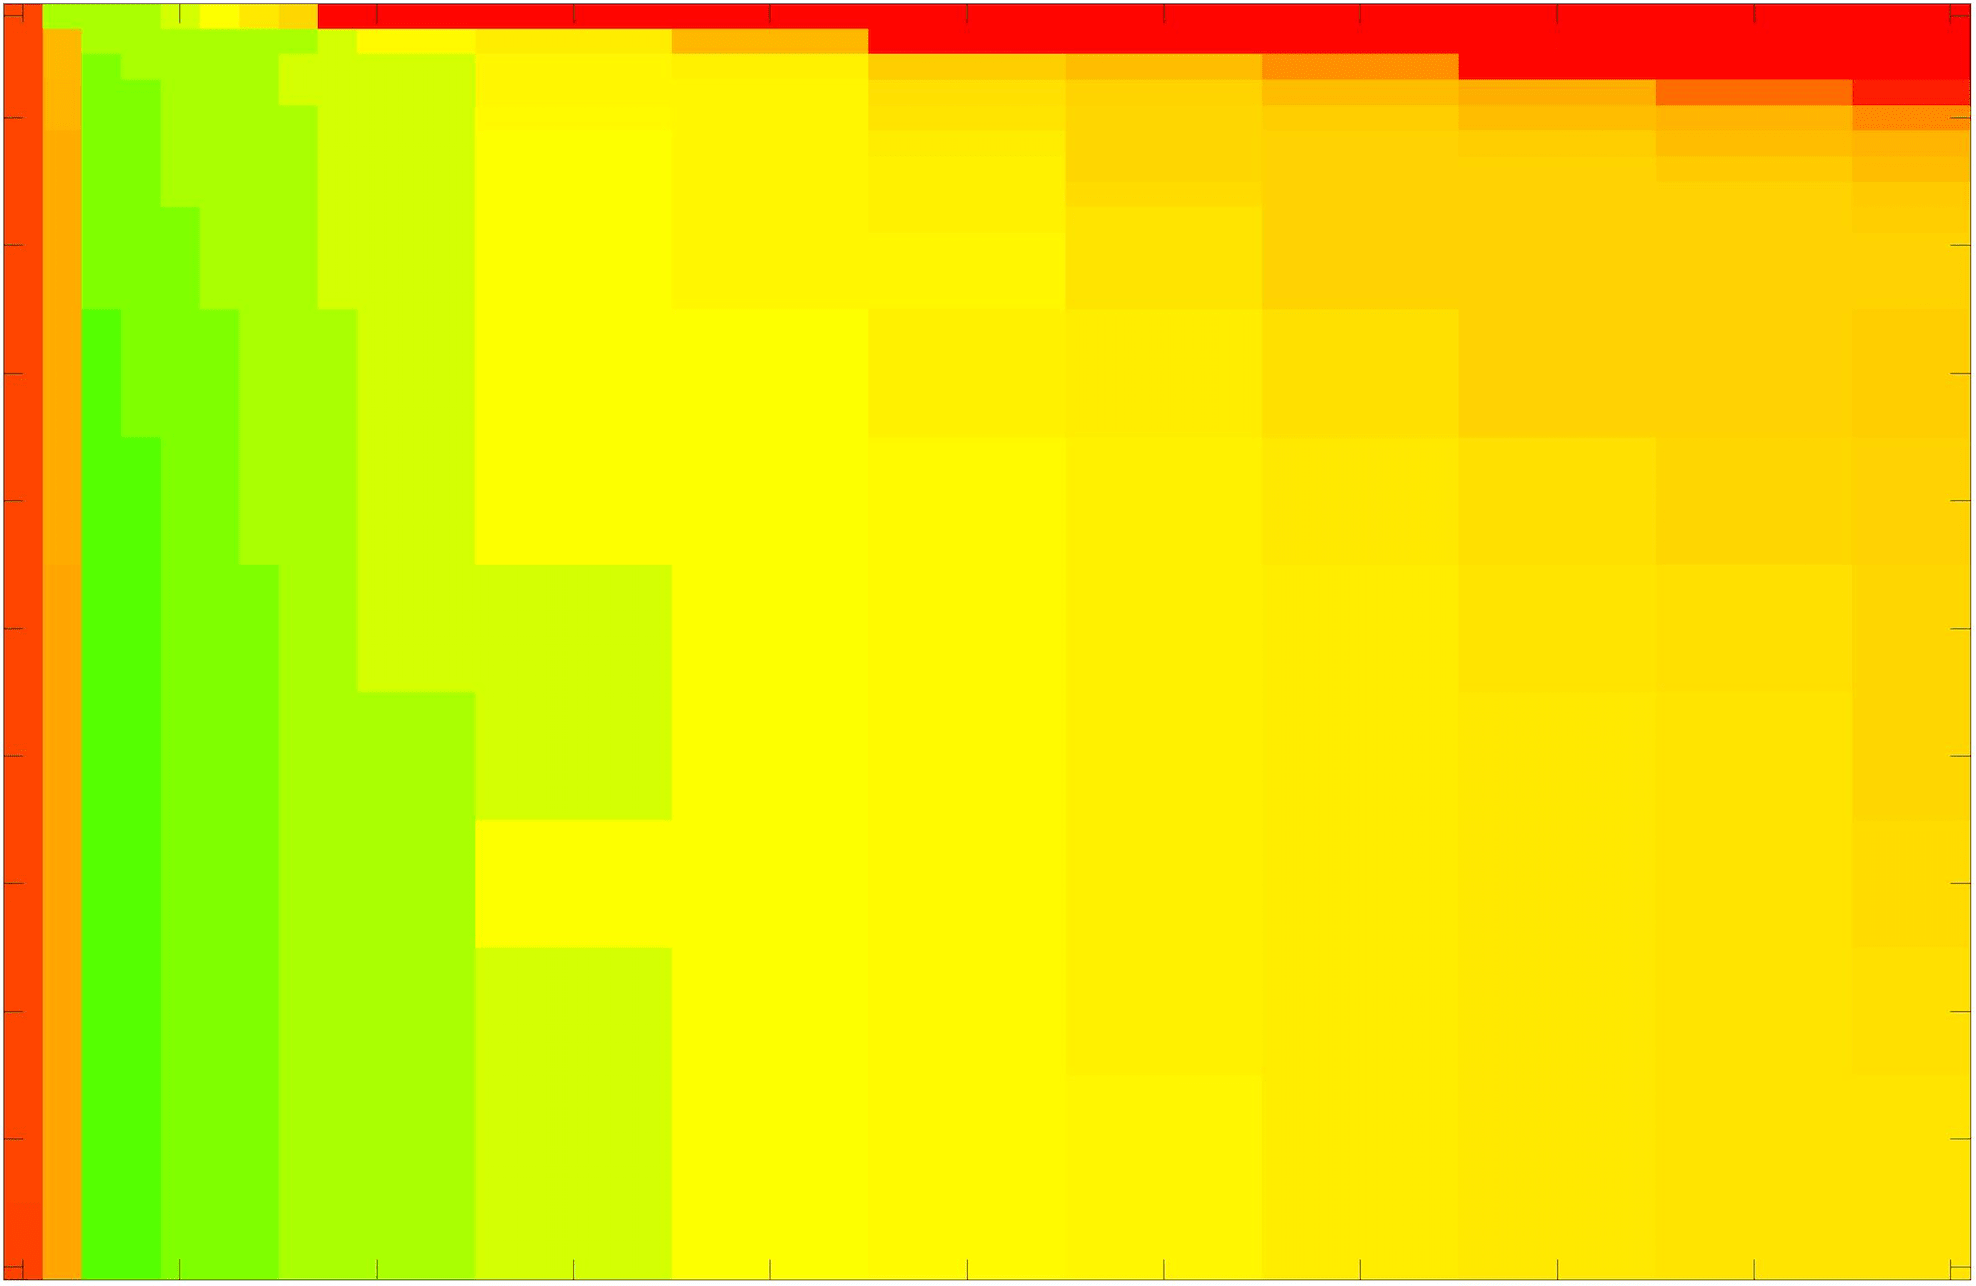

In these tests we aim to demonstrate how sensitive to parameter choices each choice of fitting term is. To accomplish this we perform the segmentations for each of the models discussed (CV, RSF, LCV, HYB, GAV) and the proposed model for a wide range of parameters and compute the TC value. The parameter range used is . Due to computational constraints, we run for each integer between 1 and 10, and every fifth from 15 to 50. This aspect of a model’s performance is vital when used in practice. The less sensitive to parameter choices a model is the more relevant it is in relation to potential applications. It should be noted that we neglect to test the selective models detailed in §3 with respect to parameter robustness as we are using the authors’ implementation of each approach. Instead, we make direct comparisons in the following sections.

The TC values for the parameter sets are presented as heatmaps in Figs. 11–13. A heatmap is a convenient way to display accuracy results for hundreds of tests concisely. In Fig. 9 we give an example heatmap with the same axes used for those in Figs. 11–13. For each of the combinations of parameter values we give the TC value of the segmentation result and represent it by the appropriate colour. The corresponding colour scale is shown in Fig. 8. Qualitatively, the more green areas of the heatmap the more accurate the model is for a wider set of parameters. Example results for Test Image 5 when varying (with ) for the proposed model are given in Fig. 10. Here it can be seen what each accuracy result corresponds to visually.

Note. The axes have been removed from the heatmaps in Figs. 11–13 for presentational clarity. However, to be explicit, the axes used in all heatmaps are the same as those in Fig. 9.

Real Images. In Fig 12 we present results for Test Images 4–6. Here, the proposed model performs in a similar way to its competitors because these images are more typical selective segmentation problems in the sense that there is a clear distinction between the foreground and background intensities. In particular, the values in each case are: Test Image 4 , Test Image 5 , and Test Image 6 . It can be seen that the proposed model is competitive compared to previous approaches. The performance is quite poor for Test Image 5, but is arguably still the best for this challenging case. In Fig. 13 we present results for Test Images 7–9. Here the proposed model outperforms previous approaches significantly for each image. This is mainly due to the type of image considered. Specifically, the true intensities are: Test Image 7 , Test Image 8 , and Test Image 9 . The proposed model is capable of achieving results where , with other models failing completely in these cases.